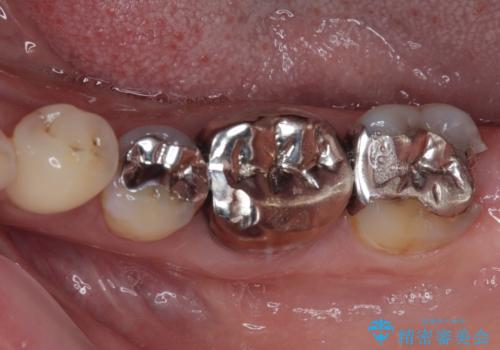

- 銀歯の奥が欠けてしまったとのことで来院された患者様です。

大きな銀歯が装着されており、その下からむし歯が広がっている状態でした。

特に症状はなく、神経組織も健全な状態であったため、むし歯を全て取り切った後にフルジルコニアクラウンにて補綴することとしました。